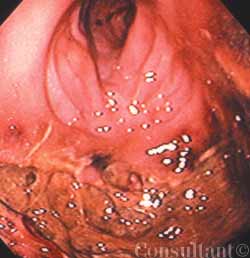

A 34-year-old white woman presentswith a 4-month history of diarrhea,with bulky, foul-smelling stools; flatulence;diffuse abdominal discomfort;and episodic nausea and vomiting. Shehas lost 13.5 kg (30 lb) during this period.The patient has had no fever, andher medical, family, and travel historyare unremarkable.